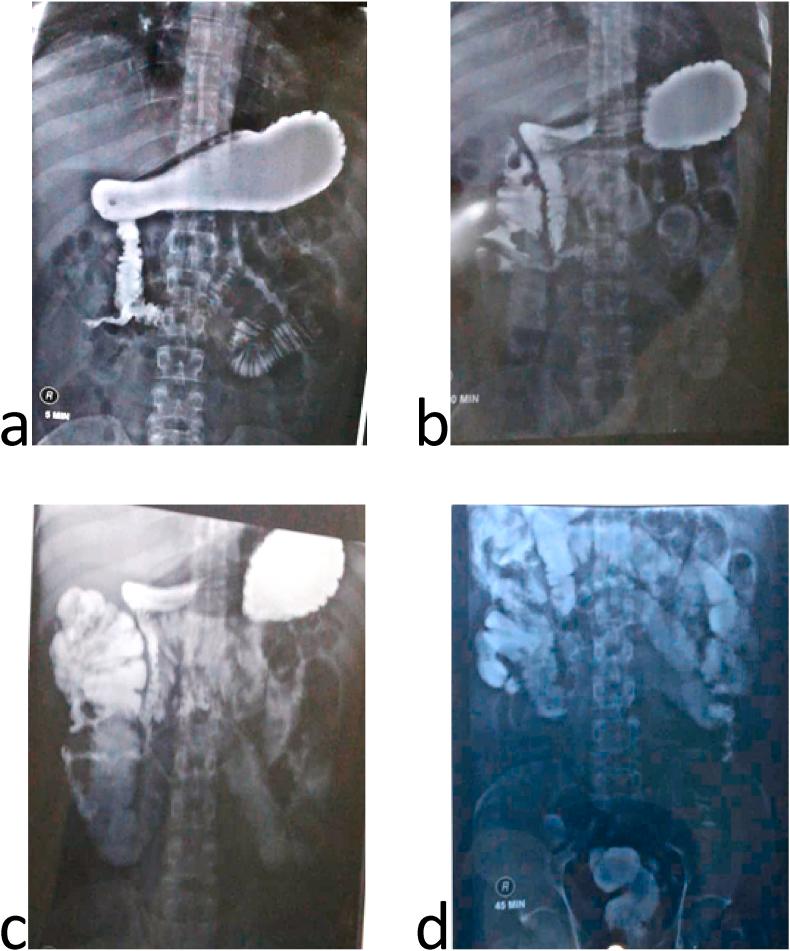

Textiloma is a retained surgical item such as a sponge or gauze that is unintentionally left in the surgical field after the wound closure. Here, we present the first reported surgical gauze that penetrated the intestine, made a duodenal-ceca fistula and then stuck far away in the ileum. Mechanical obstruction didn't appear clinically or even in radiological investigations because of the fistula which provided the intestinal continuity.

We report a 34-year-old man with a previous abdominal interventions complained of cramping, frequent vomiting and presence of undigested food in stool. The frequency of the bowel movement increased recently. Endoscopies, radiological investigations and pathological findings figure out a duodenal-ceca fistula with nonspecific inflammatory tissues in the intestinal biopsy. When we performed the abdomen surgery, retained gauze in the ileum was taken out and the duodenal-ceca fistula was fixed.

病例介绍

我们报告一名34岁男性,既往有腹部手术史,主诉腹部绞痛、频繁呕吐及粪便中有未消化食物。近期排便次数增加。内镜检查、影像学检查及病理结果显示为十二指肠-盲肠瘘,肠道活检有非特异性炎性组织。我们进行腹部手术时,取出了回肠内残留的纱布并修复了十二指肠-盲肠瘘。